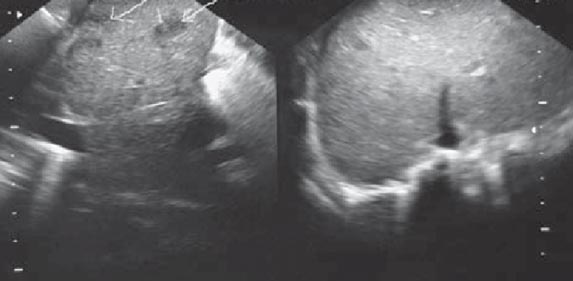

USG

Vaginal probe ultrasound is used extensively to monitor follicles during ovulation induction cycles for IVF and often for stimulated IUI. Another use is to measure the thickness of the endometrium to confirm that it is developing properly. Ultrasound is also used to document pregnancy, by visualizing the fetus, as well as detecting early fetal heart motion.